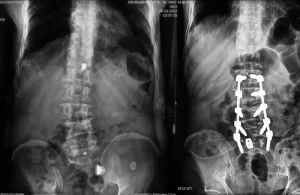

Spine surgery requires exceptional precision. Every millimeter matters because the spinal cord is the main communication pathway between the brain and the entire body. Any

In recent years, spine surgery has seen significant advancements, thanks to the integration of cutting-edge technologies. One of the most impactful innovations is O-arm guided

Spine surgery has evolved dramatically over the past few decades, moving from traditional open techniques to minimally invasive procedures that prioritize patient safety, precision, and